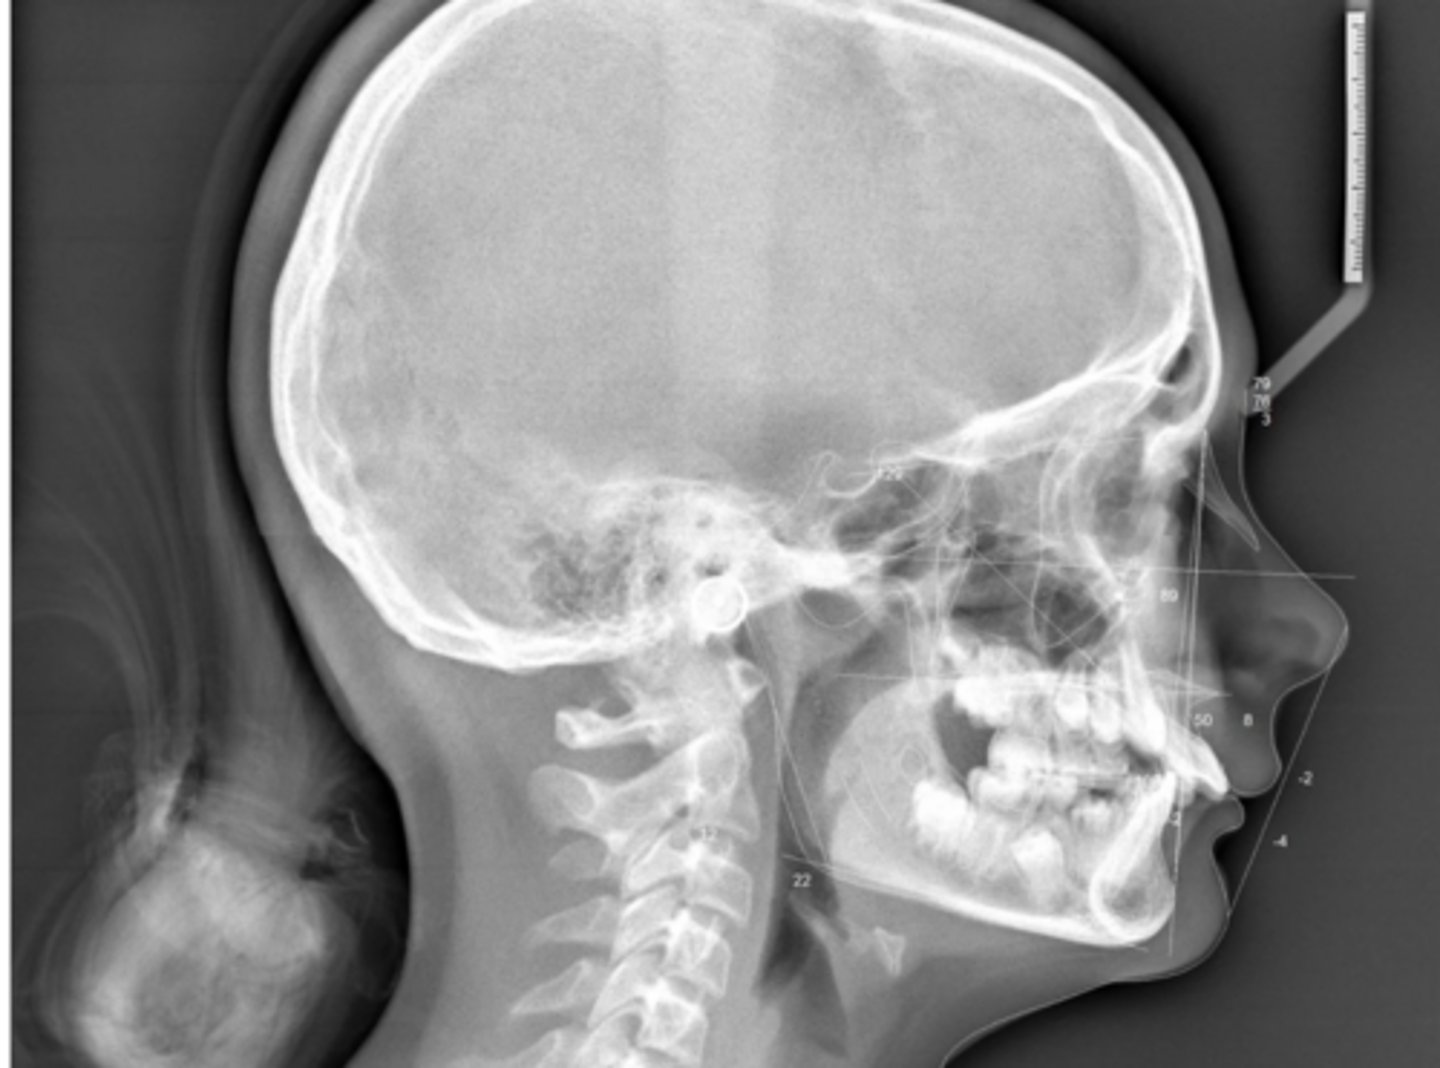

Class II skeletal (very light)

What type of skeletal malocclusion is this patient?

Hypodivergent

Are the hyper-, hypo-, o normo- divergent?

proclined

Maxillary incisors are?